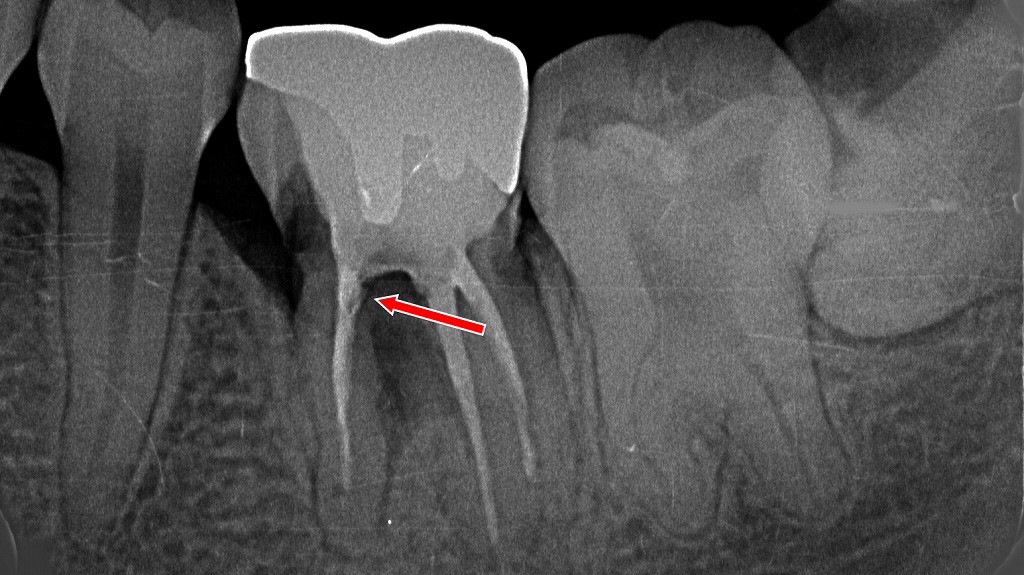

① 1枚目:ファイル挿入による根管長測定

内容のポイント

- 根管内にリーマー(ファイル)が挿入され、根管の長さ(作業長)を測定している状態。

- 矢印上部では、病的歯根吸収により歯根外側が不規則に溶けた透過像が確認できる。

- 外部吸収がある症例では、根尖形態が不明瞭になりやすく、適切な作業長決定が特に重要。

② 2枚目:根充後の状態(治療完了時)

- 根管内がガッタパーチャでしっかり根充された状態。

- 吸収部位(矢印)は根尖周囲に透過像として残るが、

→ 感染源の除去が適切に行われ、内部から封鎖されていることが確認できる。 - 吸収歯の根管治療としては良好なシールが得られている像。